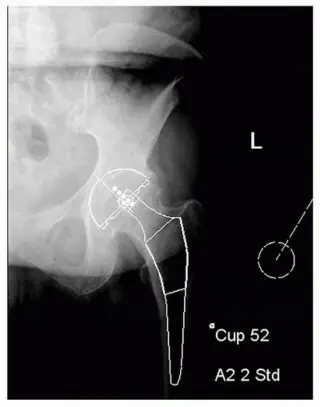

تُستخدم صور الأشعة الأمامية الخلفية للحوض (AP view of the pelvis) مع وضع الساقين في دوران داخلي بمقدار 15 درجة لتقييم عنق الفخذ بشكل صحيح وتحديد إزاحة الفخذ.

يتم قياس تباين طول الساق (LLD) قبل الجراحة من خلال الأشعة السينية. يتبع التخطيط تسلسلًا جراحيًا نموذجيًا: الحُق أولاً ثم عظم الفخذ. يتم وضع الحُق على مستوى "الدمعة" (teardrop) مع حوالي 40 درجة من الاختطاف (abduction) والتوسيط باتجاه الخط الحرقفي الإسكي (ilioischial line). يتم تحديد الحجم من خلال التغطية الجانبية الكافية دون إزالة العظم تحت الغضروفي الزائد.

الهدف من تخطيط الفخذ هو التنبؤ بالزرعة ذات الحجم المناسب لقناة الفخذ، والتنبؤ بطول قطع العنق، واستعادة إزاحة الفخذ، ومساواة طول الأطراف. يتم إعادة تأسيس طول الساق عن طريق وضع مركز دوران رأس الفخذ فوق مركز دوران مكون الحُق للطرف القصير، وأسفل مركز مكون الحُق للطرف الذي يحتاج إلى تقصير.

أظهرت دراسات متعددة أن التخطيط الجيد يمكن أن يتنبأ بتصحيح تباين طول الساق في أكثر من 90% من المرضى، وأن تباين طول الساق سيكون أقل من 1 سم في غالبية المرضى (13,14,15). الأخطاء الأكثر شيوعًا في تنفيذ القالب هي الإطالة بسبب وضع الكأس السفلي وزيادة الإزاحة بسبب عدم كفاية التوسيط (16).